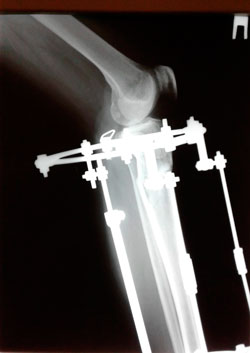

в процессе работы